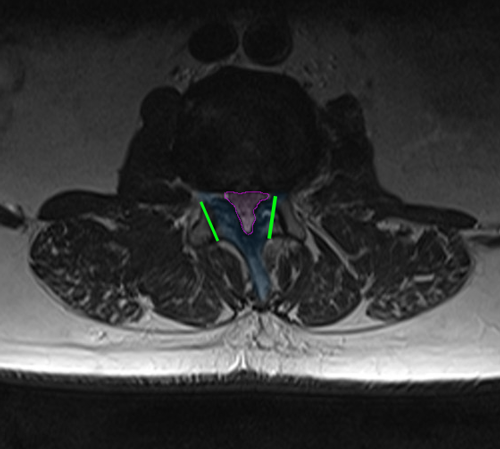

LumbarLaminectomy

Στένωση οσφυϊκού σπονδυλικού σωλήνα (φούξια). Τα όρια της προγραμματισμένης πεταλεκτομής αναδεικνύονται με πράσινο και συμπεριλαμβάνουν το πέταλο και μέρος των μικρών αρθρώσεων (μπλέ).